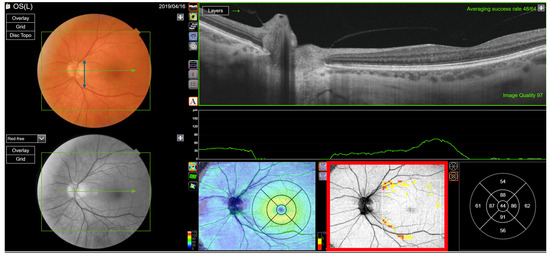

Figure 14. Ganglion cell layer analysis of a healthy left eye with a narrow macula. The vessel separation angle is narrow (blue double arrow). The ganglion cell layer thickness is normal at the centre of macula, except at the border of the vessels (red rectangle).

A correlation between RNFL- and GC-IPL-based classifications was seen in that the 26 (34%) out of the 77 eyes with type 6 annular clusters were RNFL type 2 eyes with a wide RNFL ridge separation angle (Table 7), thus showing that when the separation angle is wide, the macula tends to be thinner (Figure 13). When the separation angle is narrow, the centre thickness of the macular centre tends to be normal compared to the reference group (Figure 14).